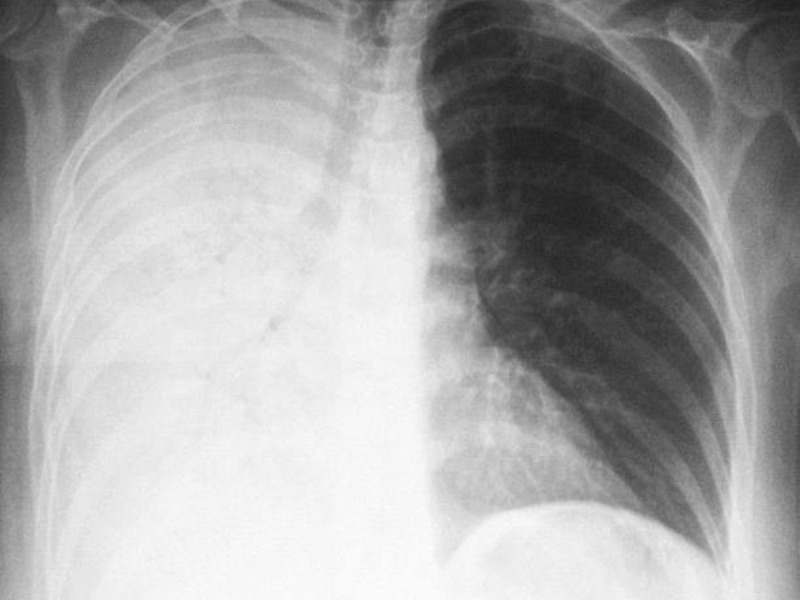

- Тотальные. Патологический процесс охватывает всю область лёгочной ткани. Сильная пневмония слева

При плеврите, на снимке скопление экссудата в поражённой области. Плеврит выступает в качестве осложнения недолеченной пневмонии.

Как правило, при крупозной форме воспаления легких поражается одна или несколько долей легких сразу. Это создает серьезную угрозу жизни пациента.

На рентгене крупозная форма болезни проявляется следующими признаками:

- Ярко выраженные крупные тени, затрагивающие доли легкого целиком. Могут быть поражены оба легкого.

- Средостение смещается в сторону наиболее воспаленного легкого.

- На куполах диафрагмы отчетливо видны признаки деформации.

- Рисунок легочной ткани может не просматриваться.

Крупозная пневмония легче всего выявляется при рентгенологическом исследовании. Тем не менее для постановки точного диагноза врачи предпочитают делать рентгеновские снимки в двух проекциях. Это дает им возможность определить число пораженных воспалением сегментов органа и определить состояние средостения.